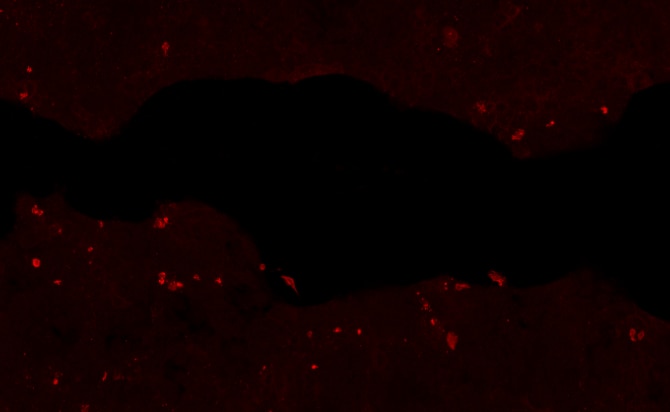

Jagged 2 in HUVEC Human Cells. Jagged 2 was detected in immersion fixed HUVEC human umbilical vein endothelial cells using Goat Anti-Human Jagged 2 Antigen Affinity-purified Polyclonal Antibody (Catalog # AF1726) at 10 µg/mL for 3 hours at room temperature. Cells were stained using the NorthernLights™ 557-conjugated Anti-Goat IgG Secondary Antibody (red; Catalog # NL001) and counterstained with DAPI (blue). View our protocol for Fluorescent ICC Staining of Cells on Coverslips.